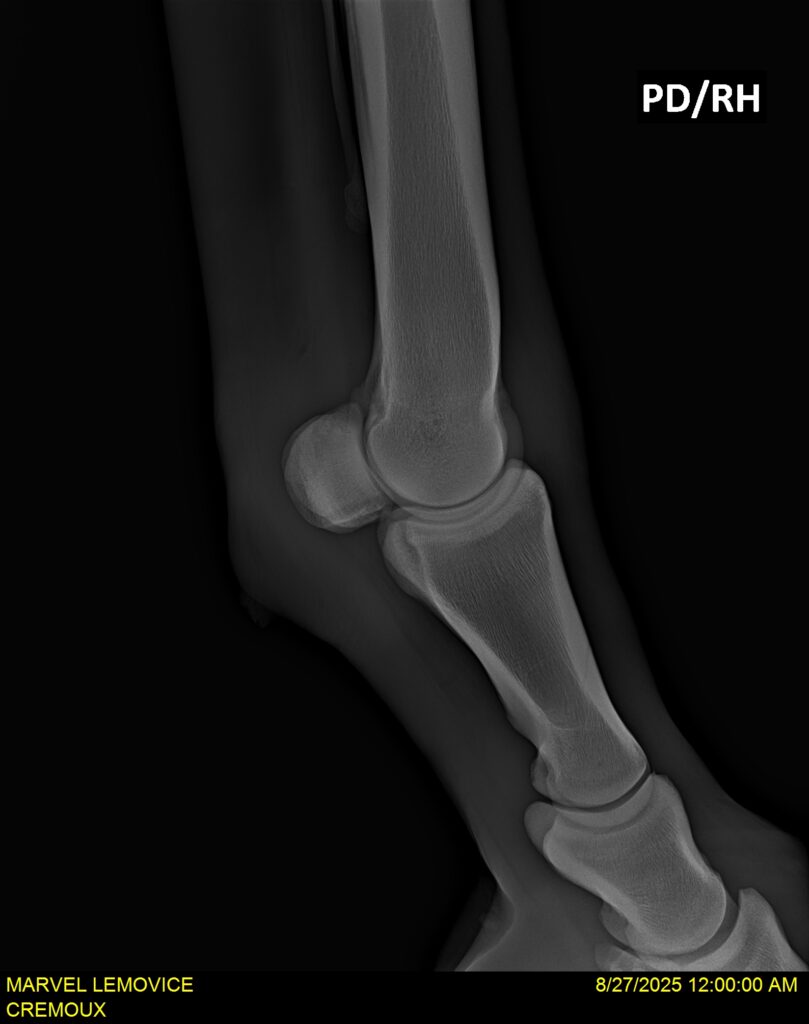

MARVEL LEMOVICE, hongre, Selle Français prend 4 ans en 2026. POPSTAR LOZONAIS x ROSIRE sur une excellente souche maternelle de l’élevage PLATIERE. Débourré aux trois allures et mise en route à l’obstacle. Super modèle avec du cadre et de la force, cheval respectueux avec des moyens. Très agréable au quotidien. Transport OK, maréchalerie OK, santé RAS, Bilan 20 clichés radios + clinique OK.

RADIOS ET CLINIQUE